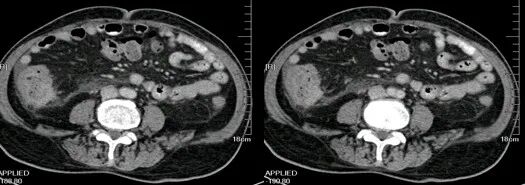

大肠癌

大肠癌是常见的恶性肿瘤,包括结肠癌和直肠癌。大肠癌的发病率从高到低依次为直肠、乙状结肠、盲肠、升结肠、降结肠及横结肠,近年有向近端(右半结肠)发展的趋势。其发病与生活方式、遗传、大肠腺瘤等关系密切。发病年龄趋老年化,男女之比为1.65:1。

升结肠癌并广泛转移

升结肠癌

升结肠癌并肝转移